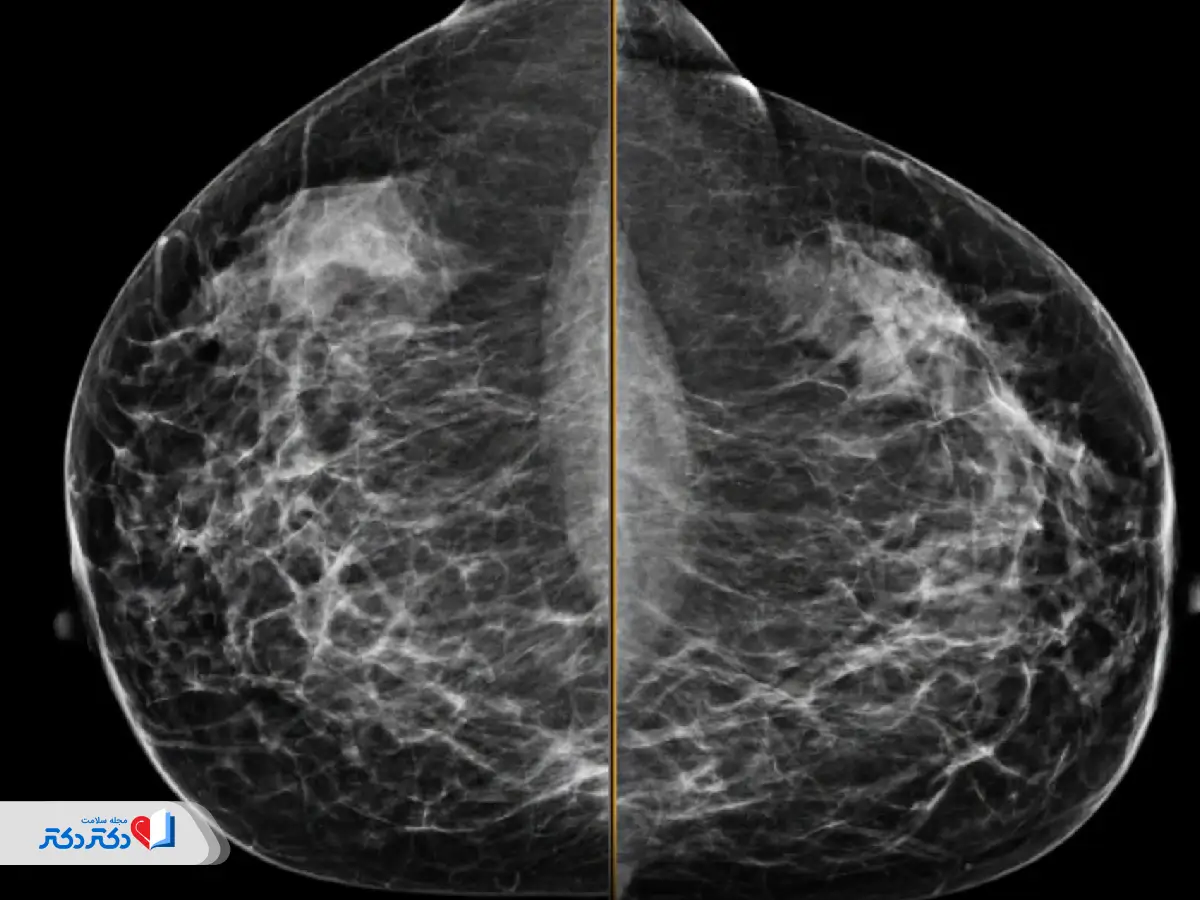

عکس ماموگرافی نرمال و مشکوک

باید بدانید که تفسیر عکس ماموگرافی و نوع عارضه احتمالی وظیفه متخصص رادیولوژی و پزشک است. به علاوه گاهی ماموگرافی بهتنهایی برای تشخیص نهایی کافی نیست؛ بهویژه در مورد خوشخیم یا بدخیم بودن توده. برای آشنایی بیشتر شما در زیر چند نمونه عکس ماموگرافی مشاهده میکنید. ولی فراموش نکنید که بسته به نوع عارضه، تراکم بافت پستان و دقت تصاویر ممکن است عکس ماموگرافی شما متفاوت از عکسهای زیر باشد.